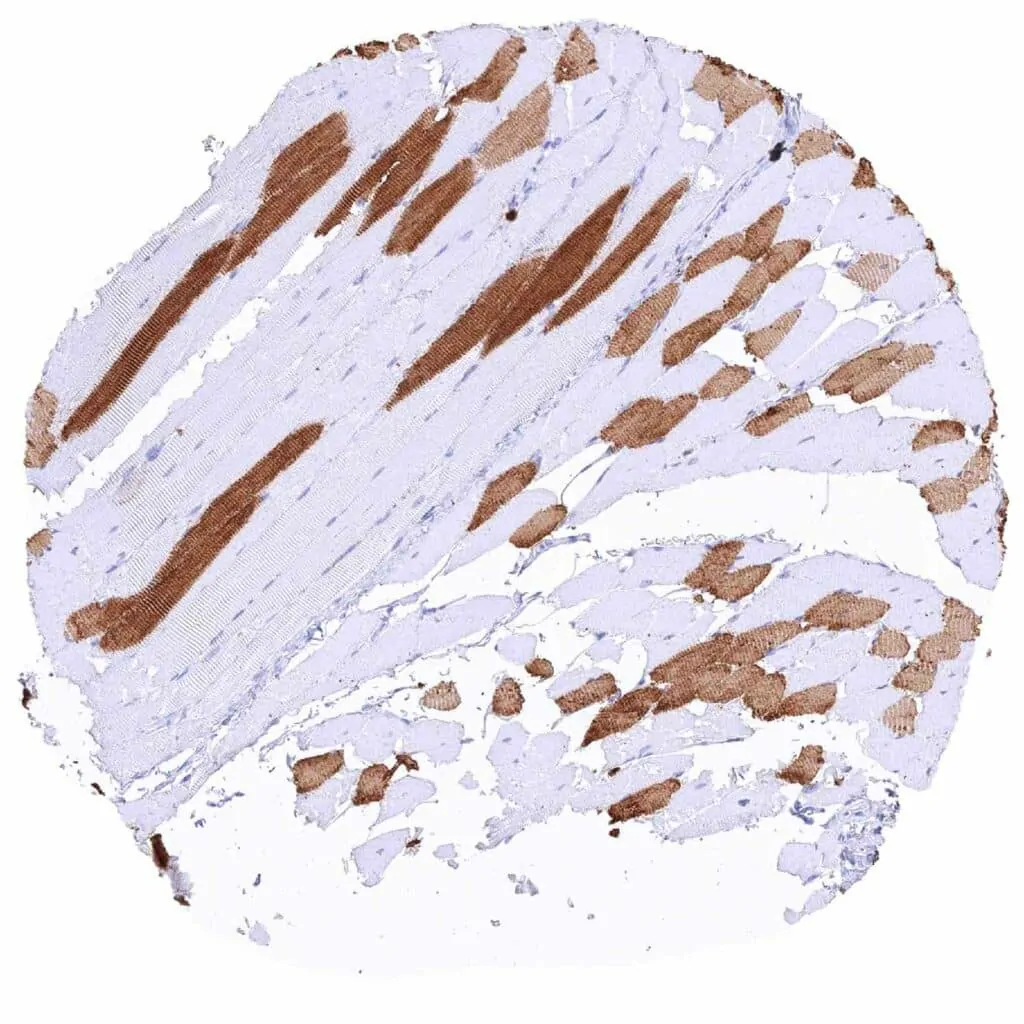

Heart muscle – Strong cytoplasmic MYH7 staining of all muscular cells